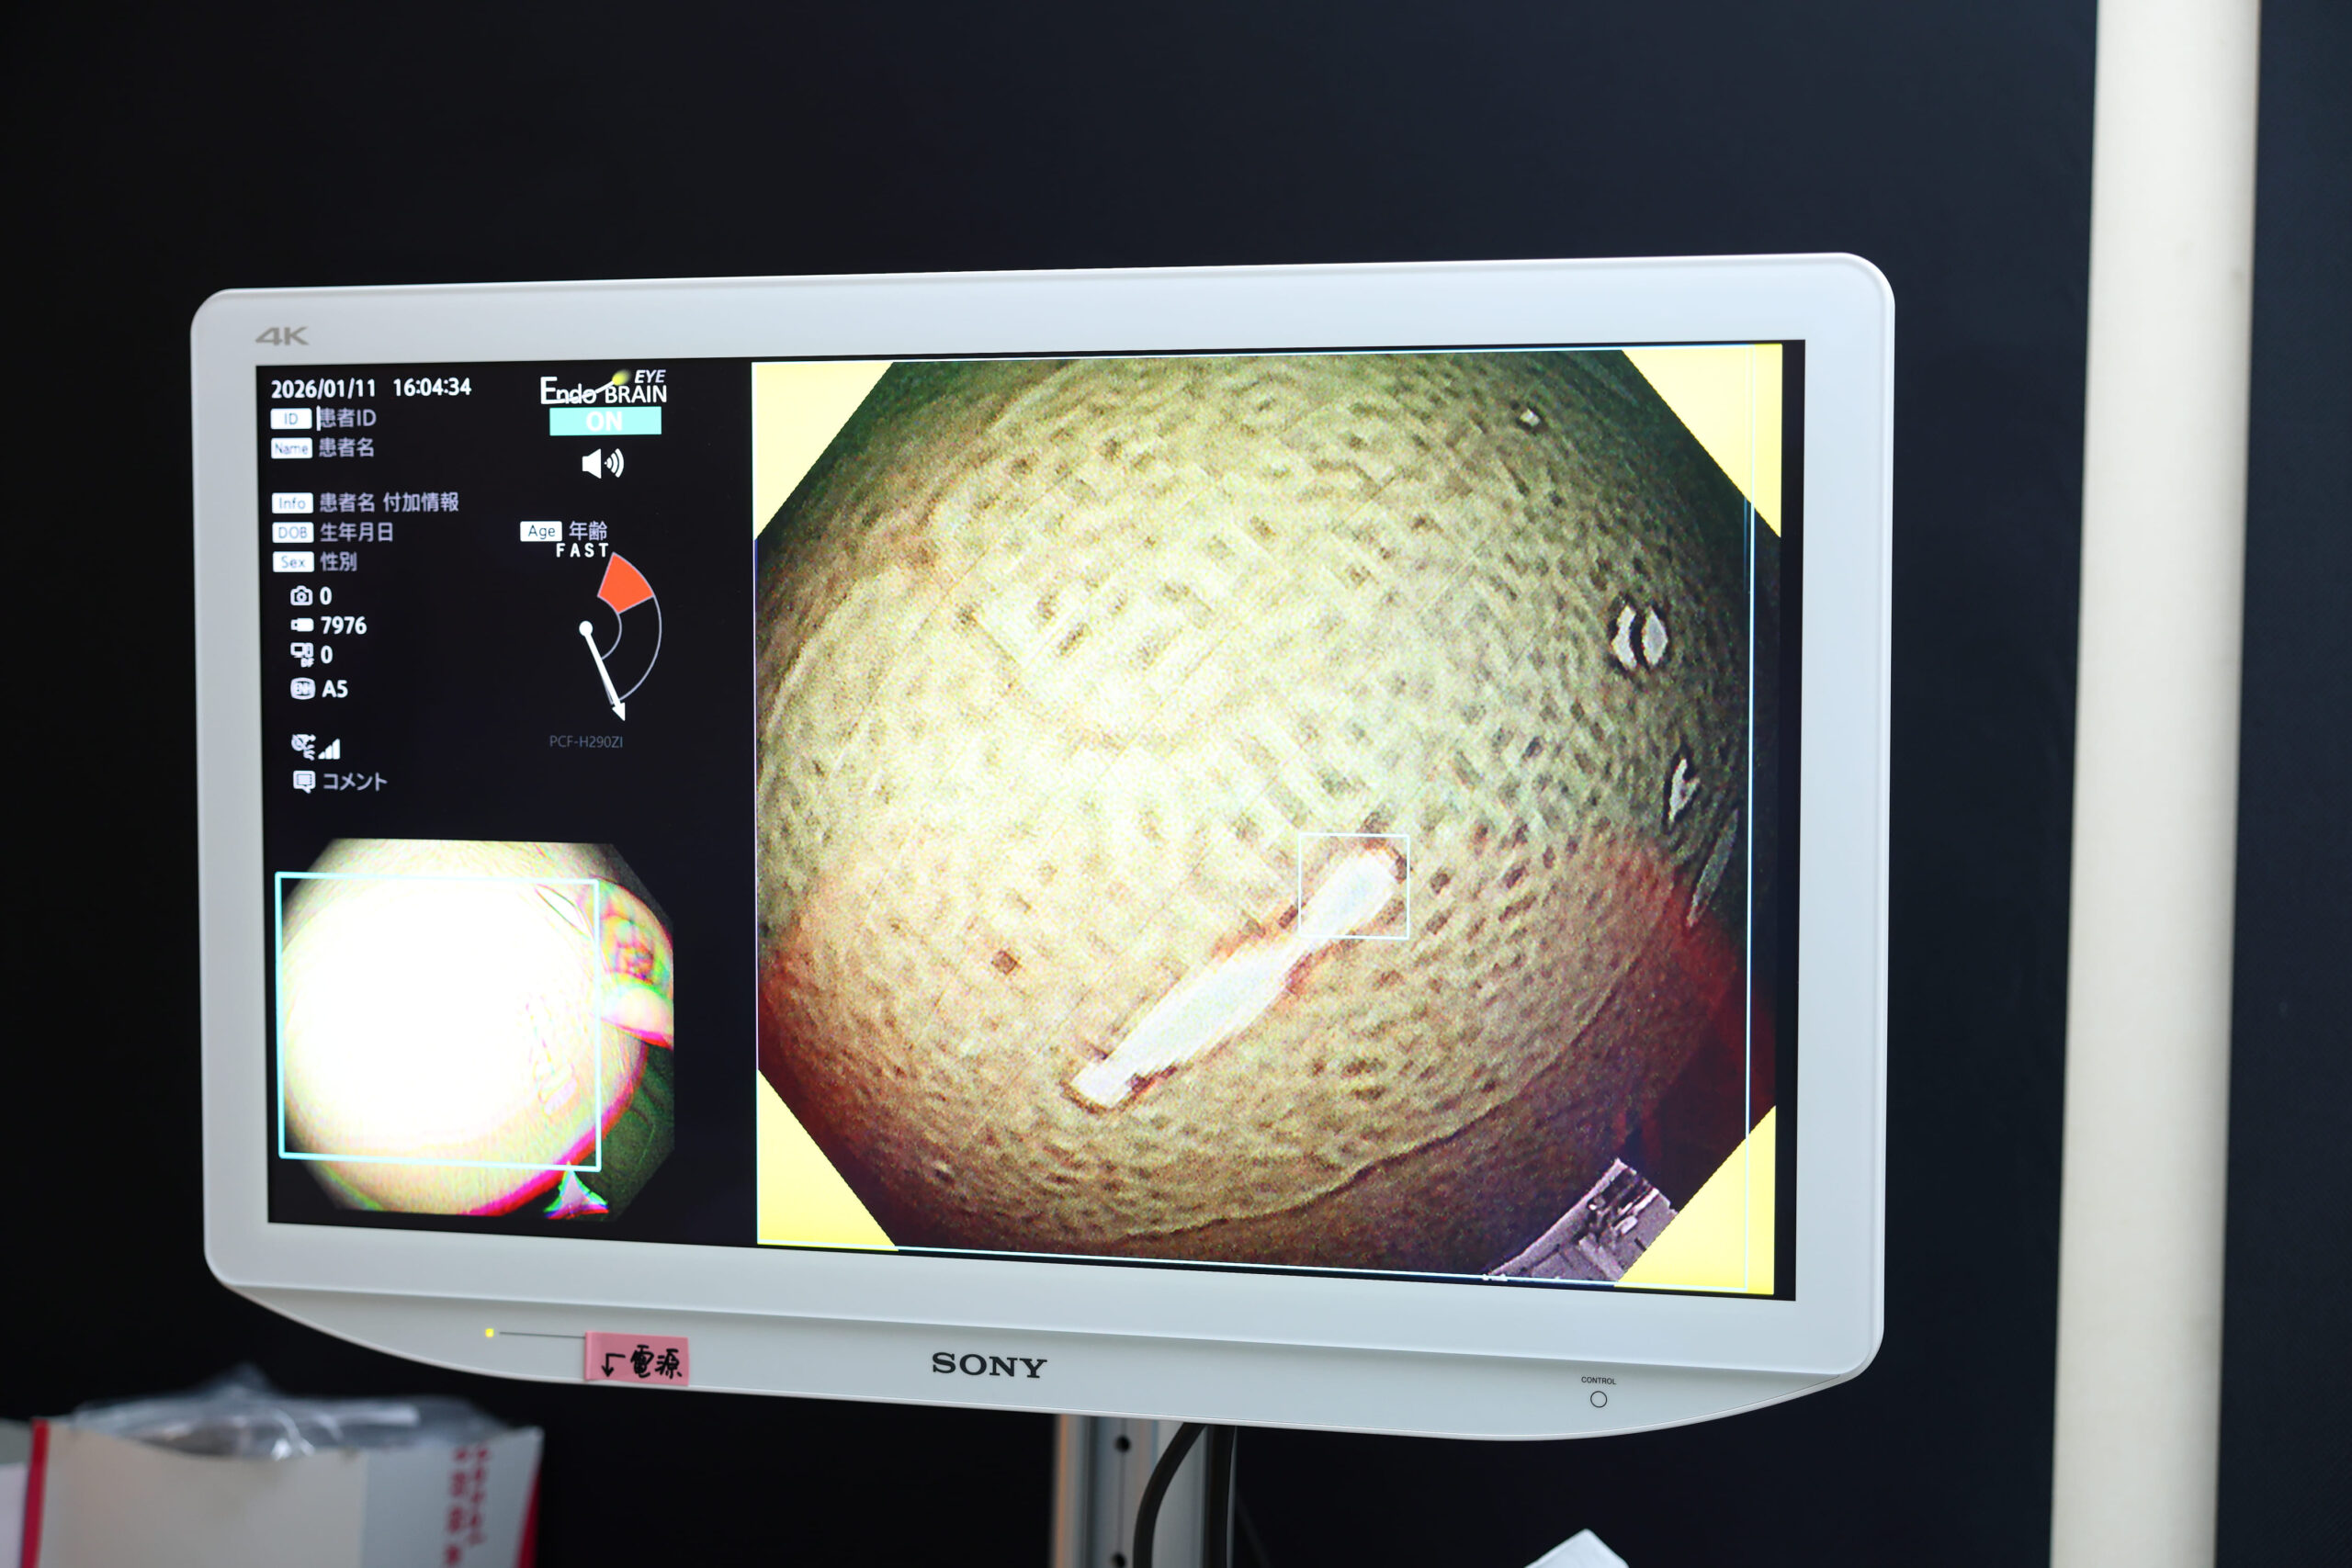

AIによる大腸ポリープ検出支援「EndoBRAIN-EYE」を導入

当院の大腸内視鏡検査では、オリンパス社製のAIによる病変検出支援システム「EndoBRAIN-EYE」を導入しております。このシステムは、内視鏡検査中に、ポリープをリアルタイムで自動検出する機能を備えています。

見落としやすい小さな病変にもAIが瞬時に反応し、モニター上に表示されることで、医師の視認を補助しながら検査精度を大幅に向上させます。

動画データから抽出した内視鏡画像を学習することで、大腸病変の検出において感度96.0%、特異度98.0%の診断支援制度があると報告されています。医師と最先端のAI技術によるダブルチェック機能により病変の見逃しを防ぎます。